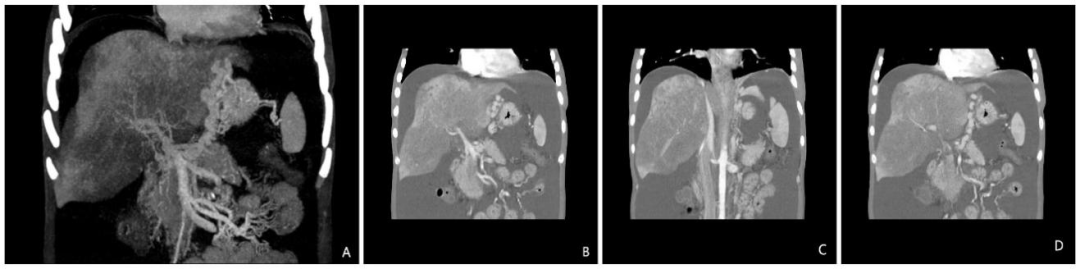

1月3次住院!61岁男性反复发热腹痛,竟揪出百万分之一的罕见消化疾病

病史摘要:61岁男性患者,因反复发热和右上腹痛1个月内3次住院。首次因发热、右上腹轻度疼痛入院,血培养检出大肠埃希菌;第二次出院4天后因高热、右上腹轻度疼痛再次入院,血培养仍为大肠埃希菌;第三次出院3天后因高热、右上腹痛加重入院,血培养依旧是大肠埃希菌。 诊疗过程:首次及第二次入院均用哌拉西林 - 他唑巴坦治疗,第三次入院实验室检查炎症指标变化大,血培养仍为大肠埃希菌